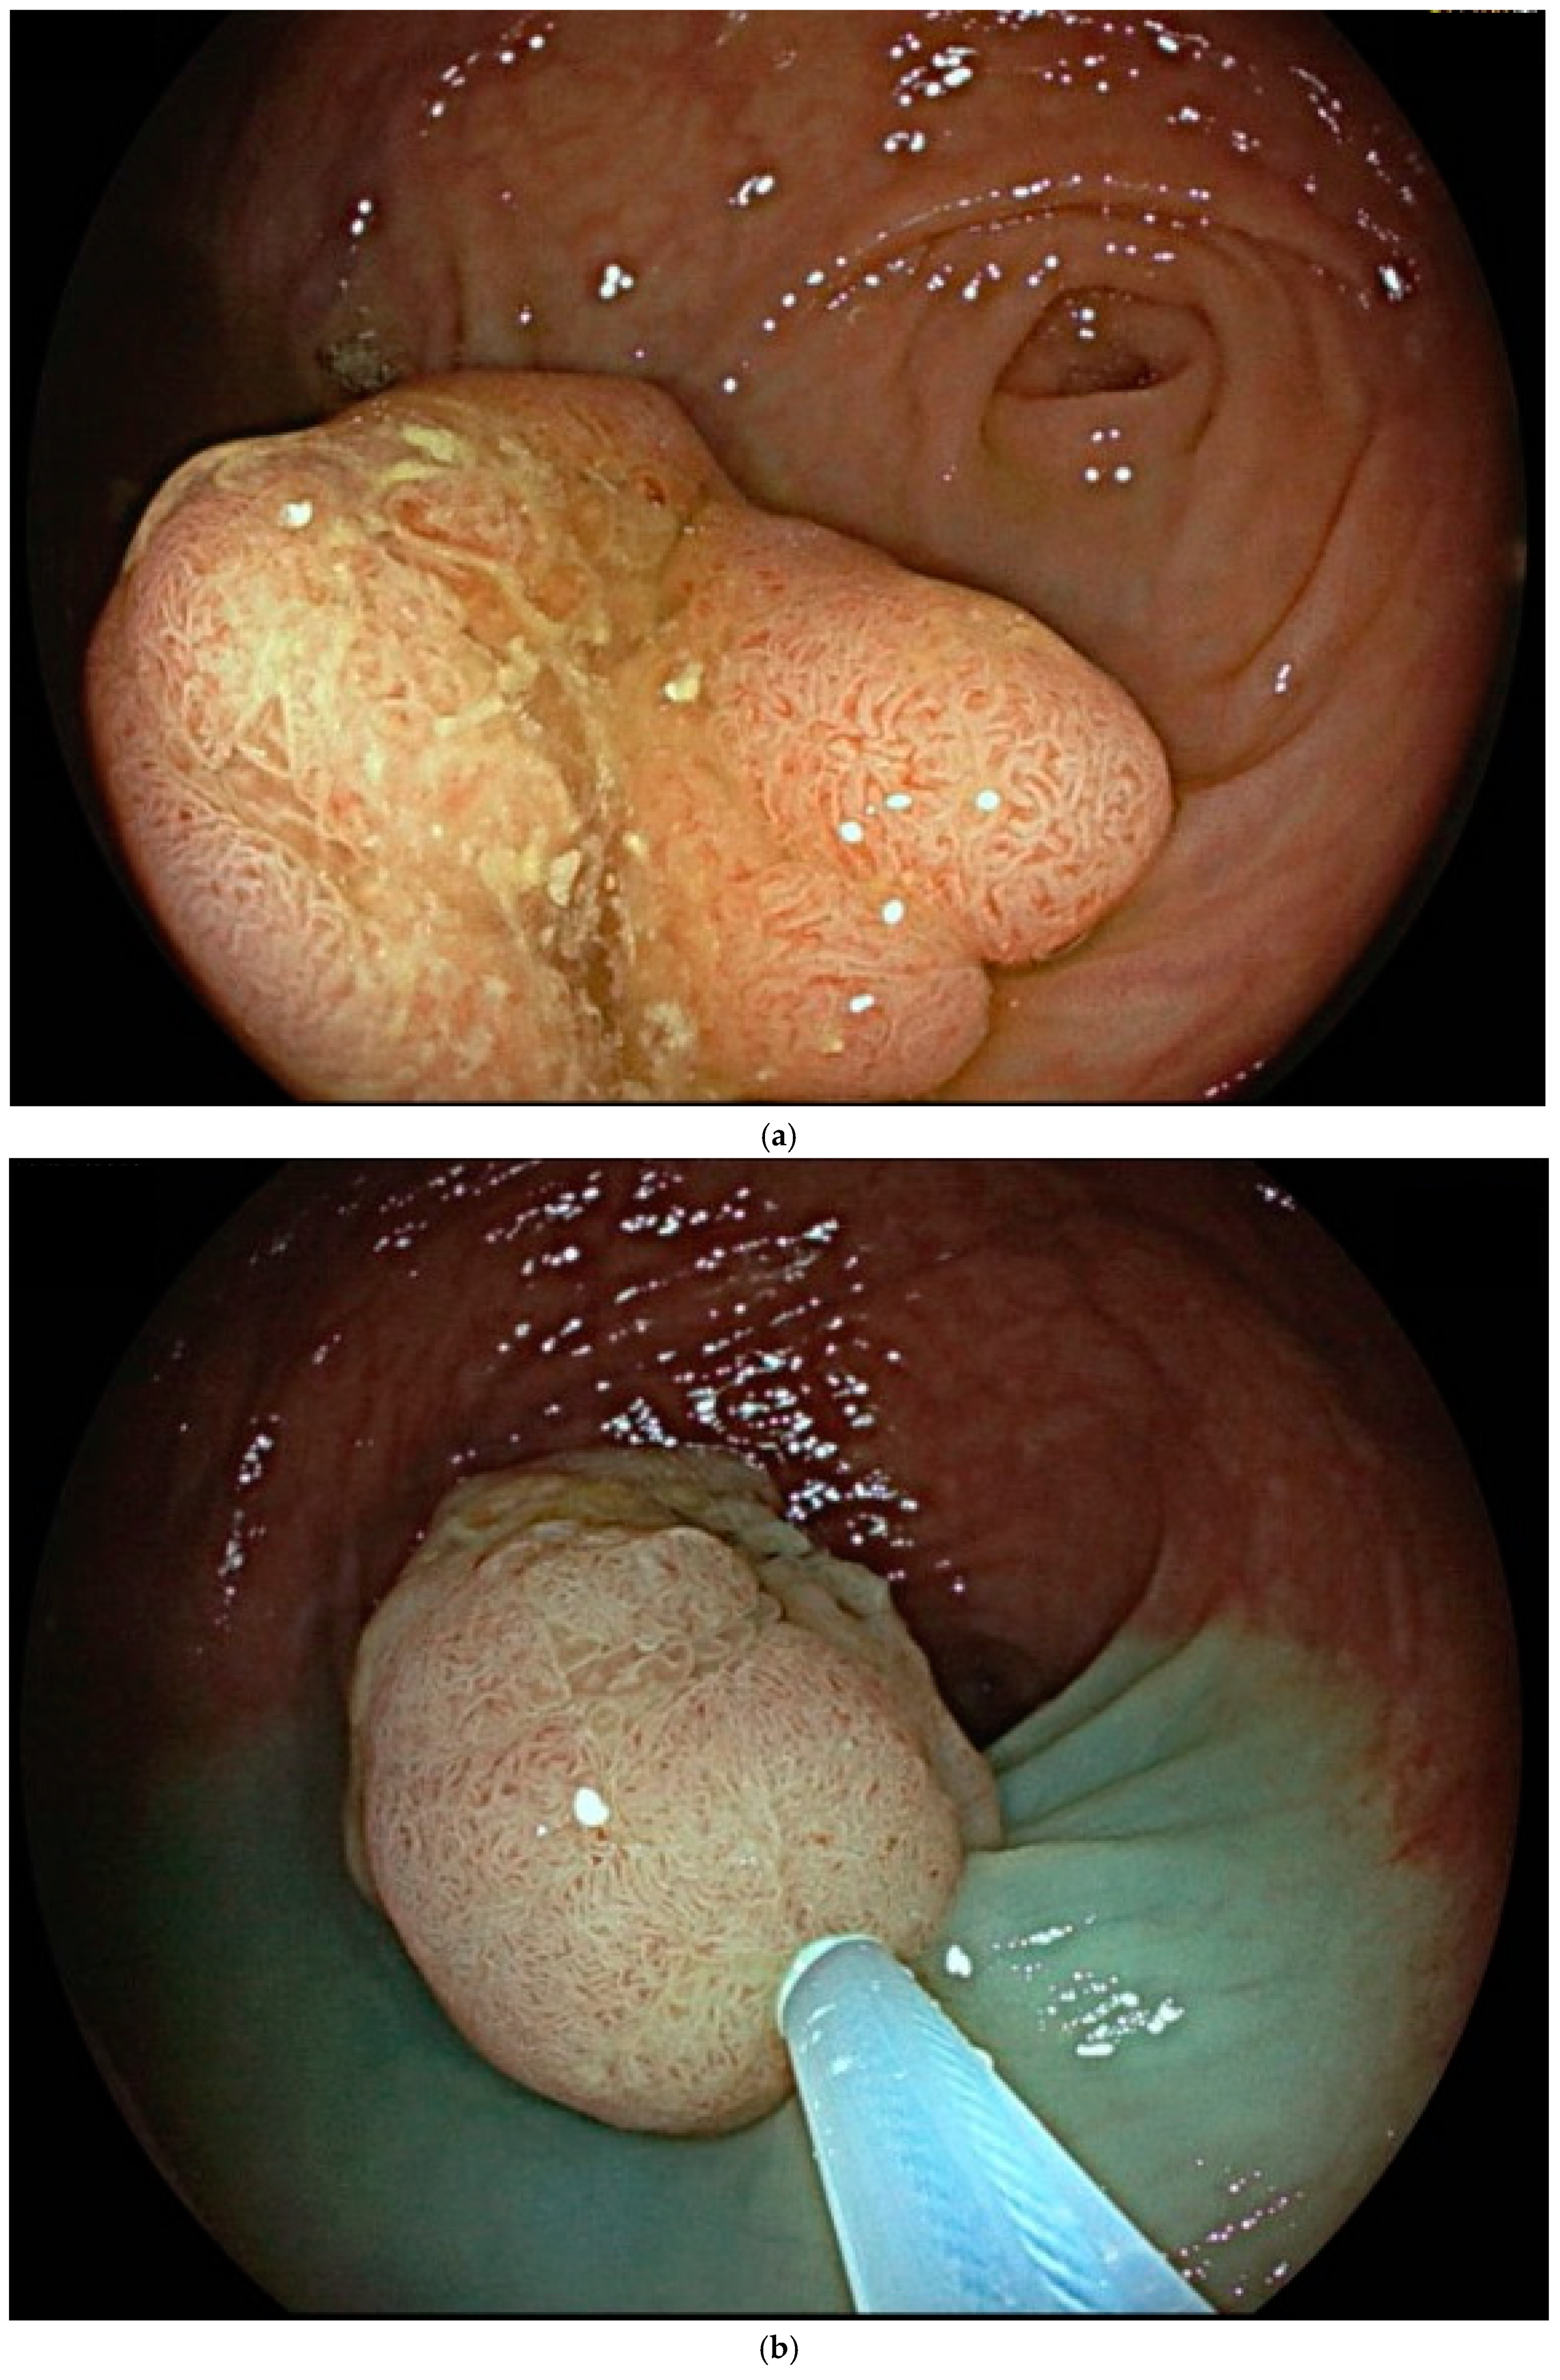

7. Endoscopic Assessment

8. Endoscopic Resection Techniques

| Endoscopic mucosal resection (EMR) involves injection of a solution into the submucosal space in order to separate the mucosal lesion from the underlying muscularis propria. The lesion can then be resected by snare electrosurgery. The submucosal cushion theoretically reduces the risk of thermal or mechanical injury of the underlying muscularis propria [81]. | ![]() |